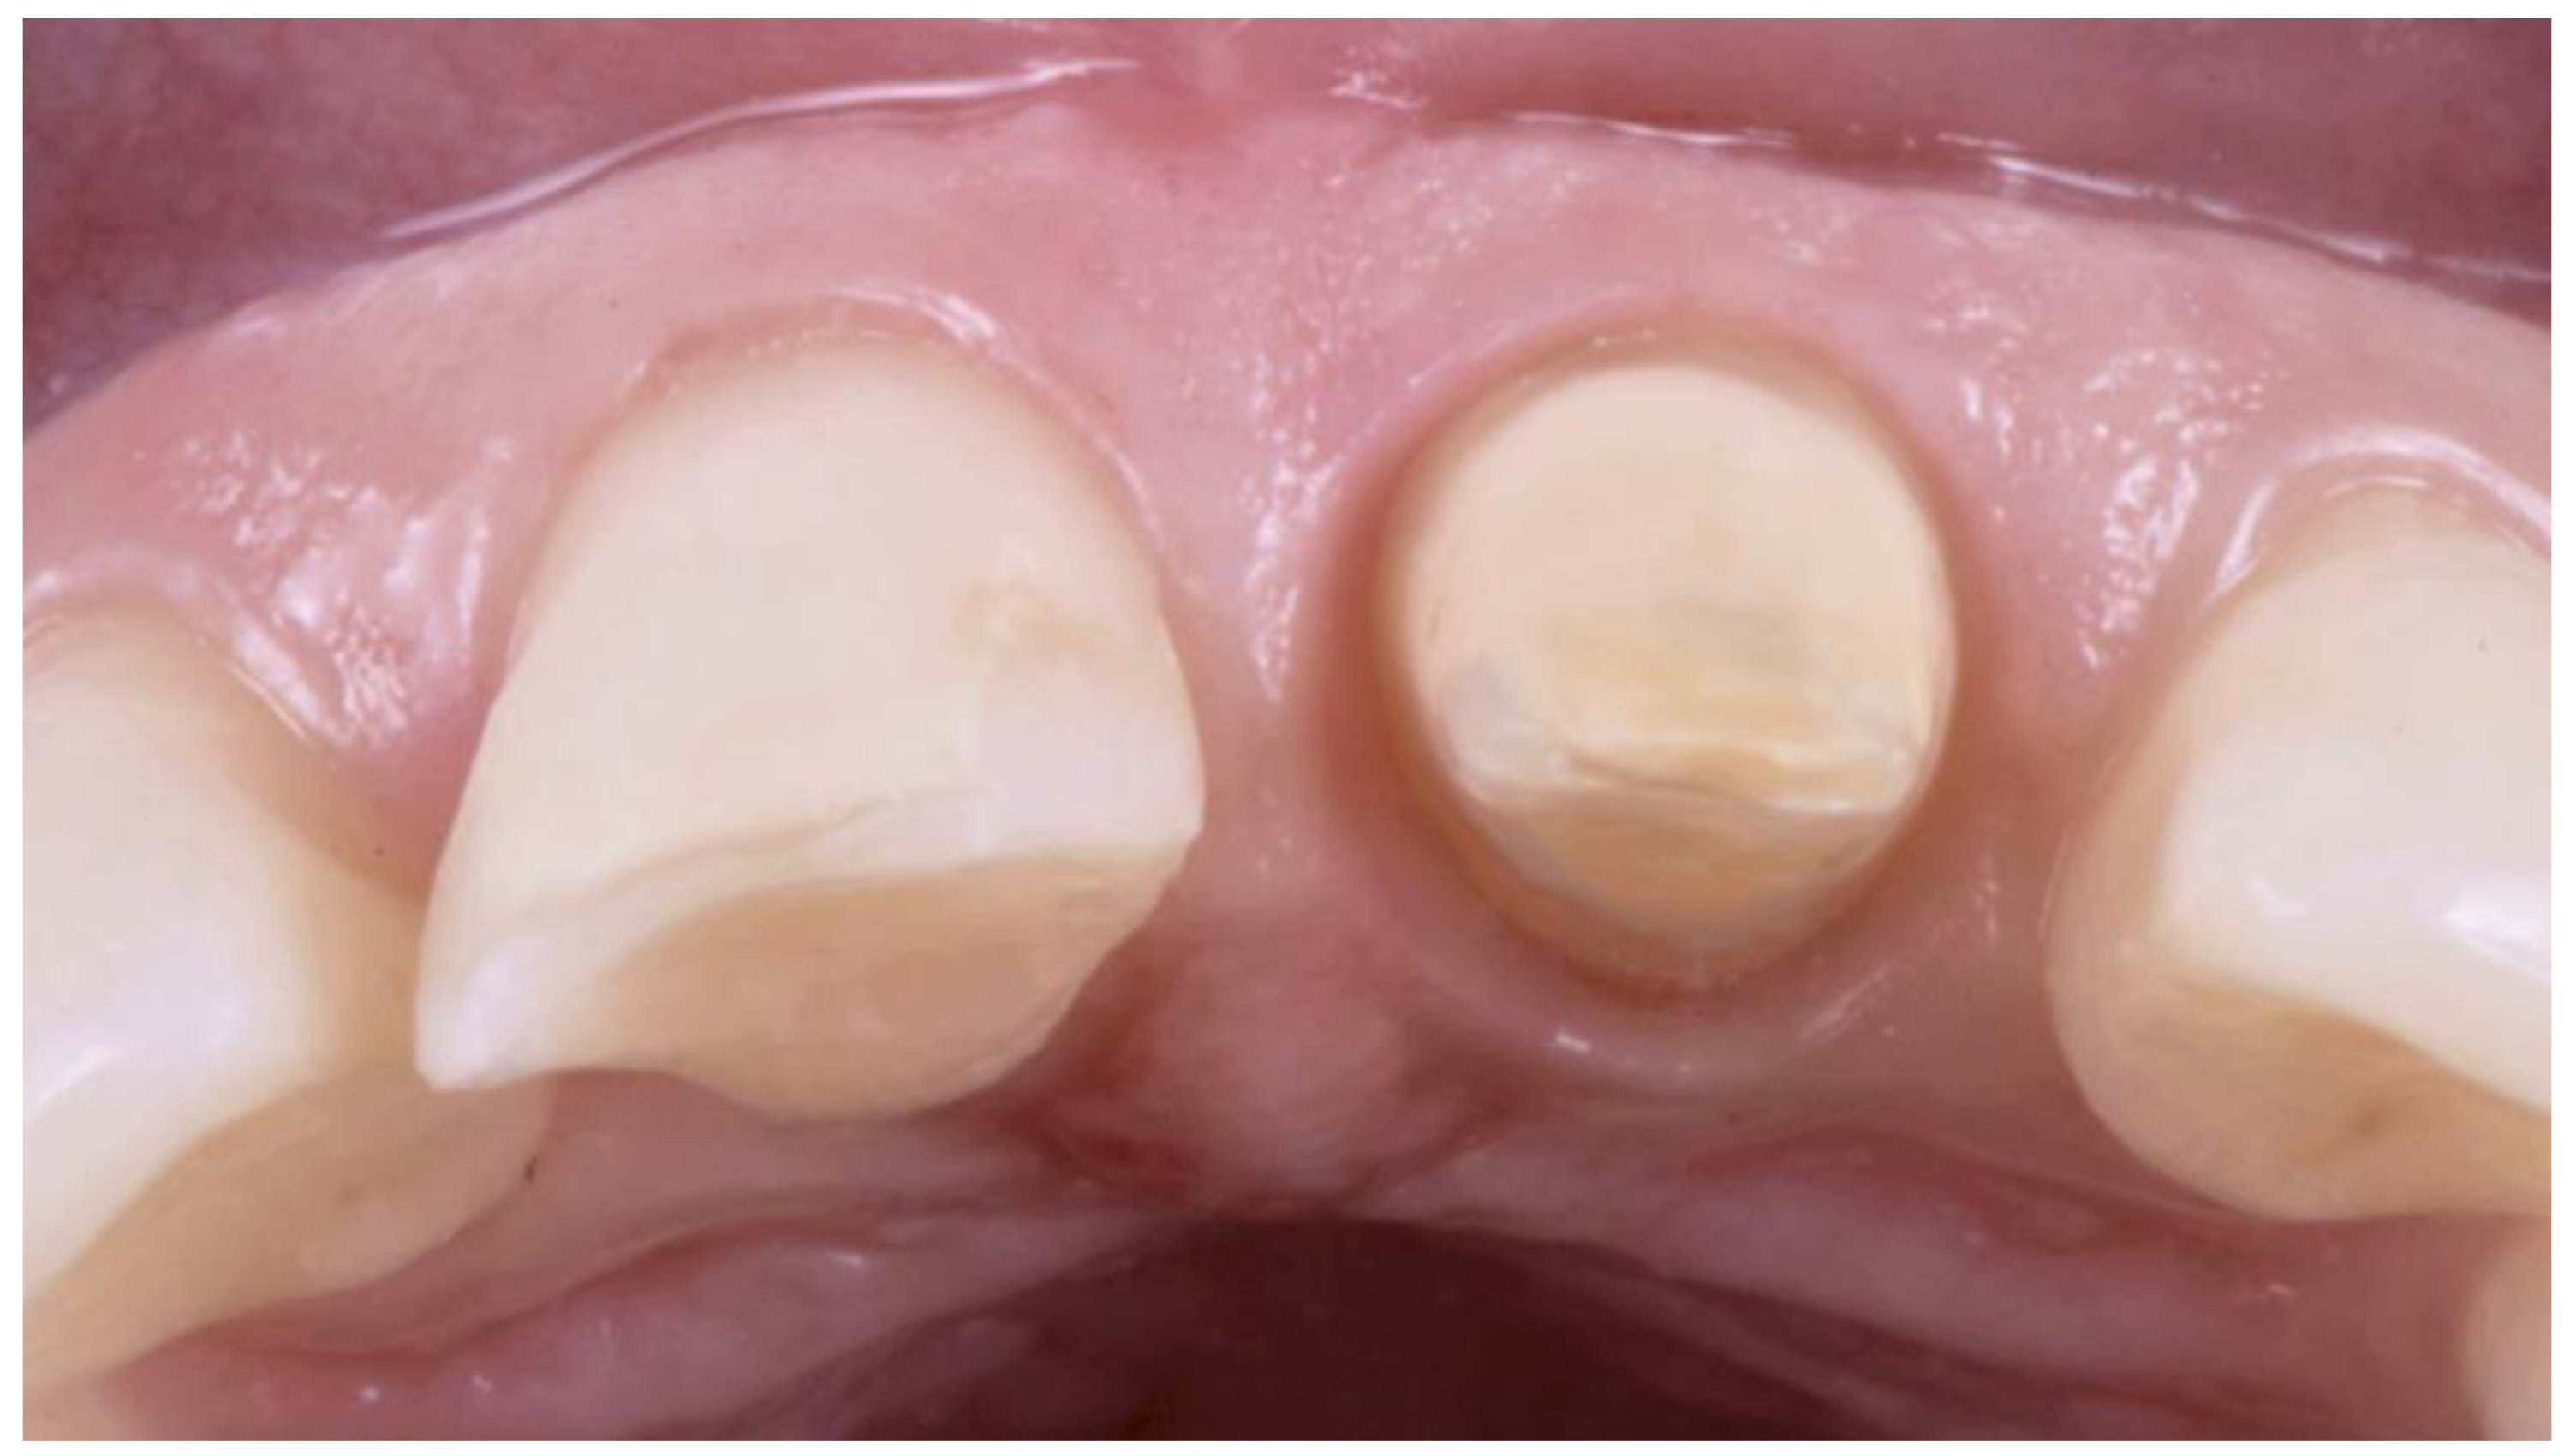

- Primary progressive reduction: This procedure is performed by using the bur with an inclination of 30° so that only the final part of the bur is in contact with the tooth structure. The bur is kept more coronal than the previously measured depth of the gingival sulcus of that site. In this way, the tissue of the root surface and a small component of the internal part of the gingival sulcus is removed. This reduction will result in a small step at the level corresponding to the tip of the bur. At this point, the preparation is “bur-shaped” as with most of the complete crown techniques (Figure 3).

- Secondary progressive reduction: The previously performed reduction of tooth structure and the push of the bur on the gingival margin, together with the unavoidable gingitage, will result in an augmented space between the tooth structures and the gingival margin. This allows the clinician to obtain better vision and access to the deepest parts of the sulcus and, therefore, to see and remove any calculus, steps, grooves, or undercuts from the root surfaces. Using a “toe-heel” technique, the apical part of the root surface is structured, creating the edgeless profile of this preparation. Then, the coronal portion of the abutment is reduced by using a bur with reverse angulation. In this phase, it is also necessary to connect the different reduction planes created during the various stages (Figure 4).